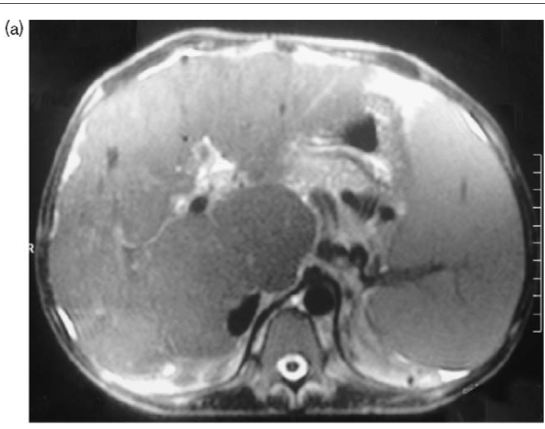

MRI of the liver corroborated the findings, revealing non-visualization of the hepatic veins and the presence of patent inferior vena cava, consistent with Budd-Chiari Syndrome. MR venography confirmed the absence of hepatic vein visualization with a patent inferior vena cava (Fig. 1a and b).

| Fig 1 MRI showing non visualisation of hepatic veins |